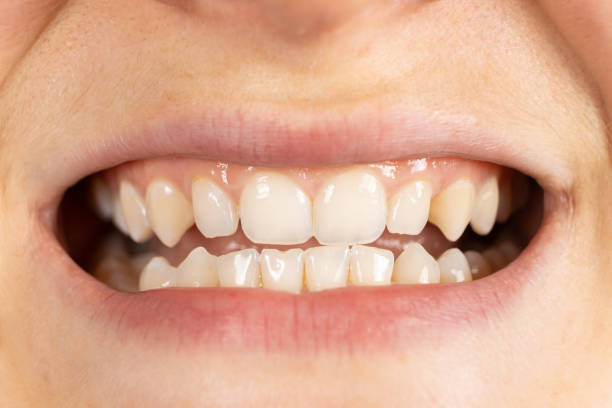

- 손가락 테스트: 입을 크게 벌리고 손가락 세 손가락을 입 안으로 넣어보세요. 턱관절 장애가 있는 경우 어려움을 겪을 수 있습니다.

턱관절 통증은 근육의 긴장이나 조임으로 인해 발생하기도 합니다. 입을 크게 벌리는 운동은 턱관절 근육의 긴장을 완화시키고 조임을 풀어줄 수 있습니다. 손가락을 입 안쪽이 아닌 바깥쪽에 대고 천천히 입을 벌리는 운동을 하면 효과적입니다. 이 운동을 반복하여 근육의 긴장을 완화시키세요.